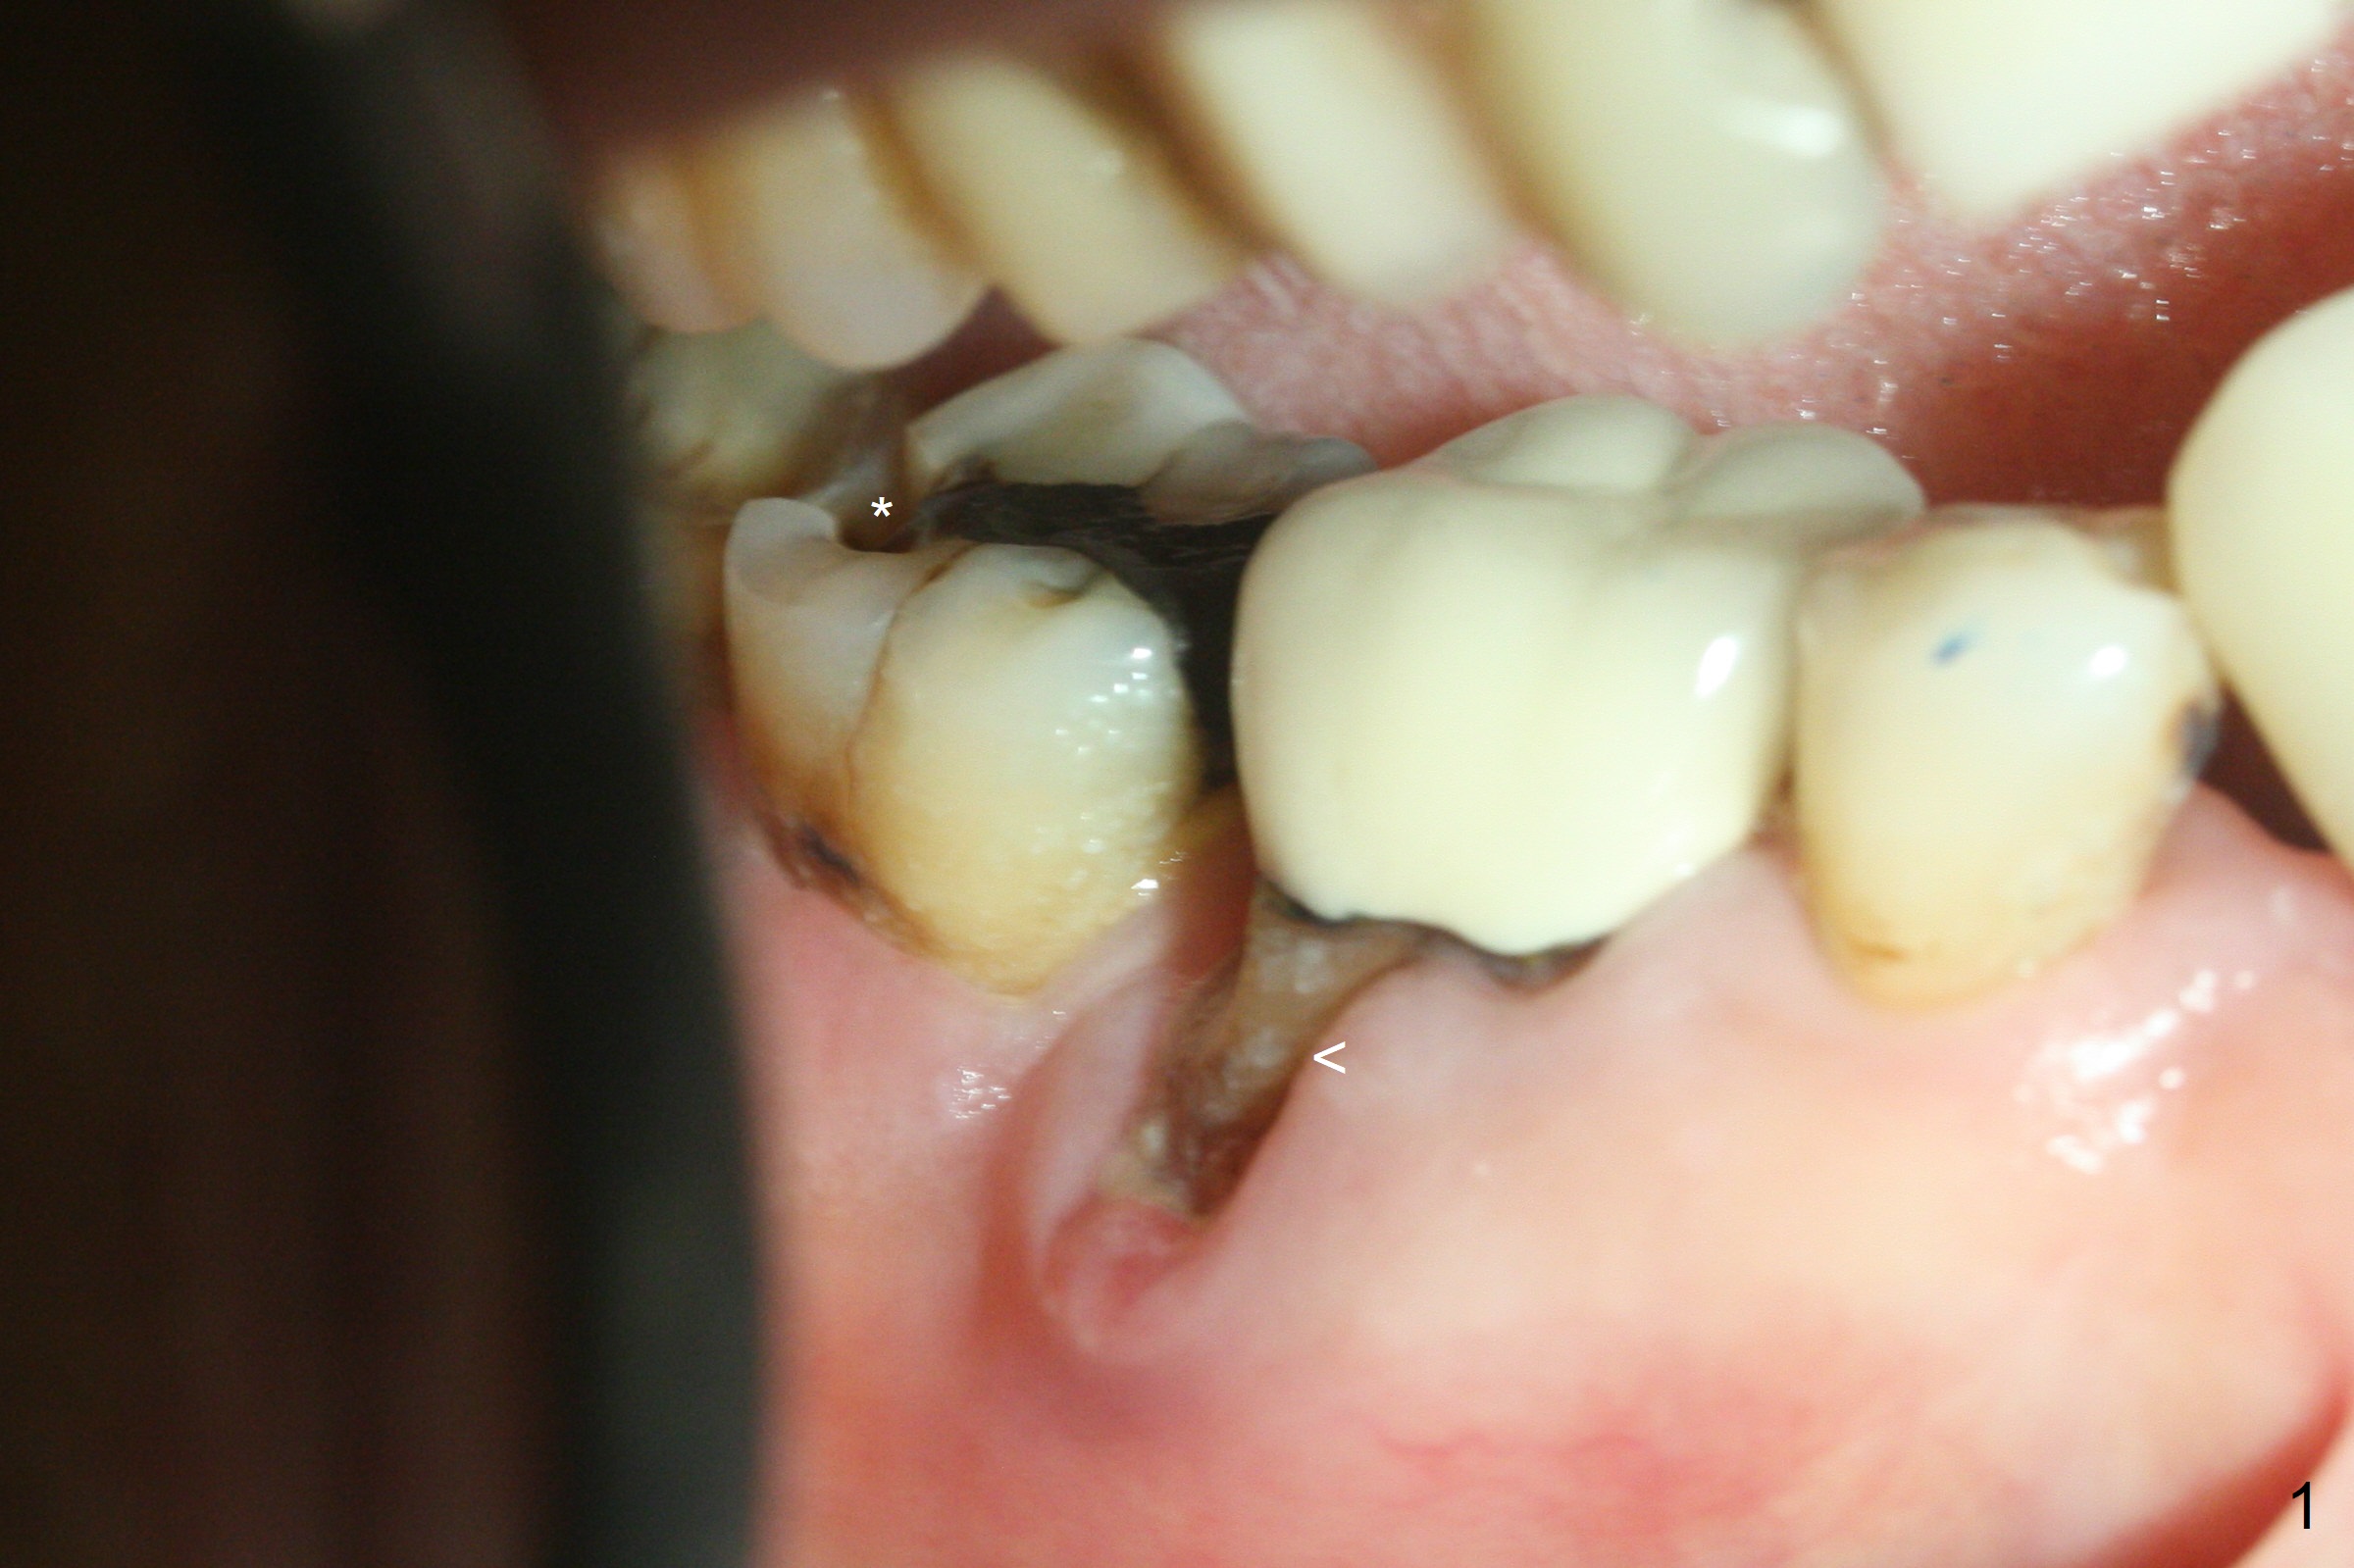

Although the tooth #30 has distobuccal root exposure (Fig.1 <), it is asymptomatic. In contrast the tooth #31 with the distoocclusal caries (*) is symptomatic. After use of 2 mm drill for 18 mm (lingual gingival margin), a calculated parallel pin is inserted (Fig.2 (D: 2 distal roots of the tooth #30)). It appears that a 11.5 mm long implant is appropriate for the site; a 5 mm cuff is expected. Following 4.8 mm drill, a 5.5x11.5 mm implant is placed initially (Fig.3) with an apical space (*) and clearance from the Inferior Alveolar Canal (red dashed line). The implant is placed deeper with placement of a 6.5x4(5) mm abutment and bone graft (*, Fig.4,5). After placement of collagen membrane over the graft, an immediate provisional is fabricated (Fig.6 P) with clearance from the opposing tooth (Fig.7 *). There is no bone loss 3.5 months postop (Fig.8). In fact the abutment has not been seated completely since its placement (Fig.4,5,8). The crown/abutment dislodges 3 years 3 months post cementation (Fig.9). The latter occurs for long incubation time because of opposing partial denture (Fig.10). After trimming proximal surfaces (Fig.11: arrowheads), the abutment remains incompletely seated (Fig.11) due to possible crestal bone interference (Fig.11 *). The smaller abutment by itself remains unseated (Fgi.12). One size small one is completely seated (Fig.13). Impression is taken. Two weeks later the abutment margin is supragingival. After screw torque at 20 Ncm, the crown is cemented with access hole. Excess cement is removed.